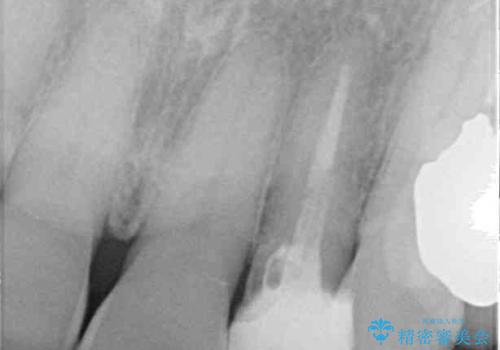

- 前歯の根管治療の際に、一時的に見た目を回復したままの状態で放置してしまったとのことで来院された患者様です。

土台の状態は良好であったため、仮歯に置き換えた上でオールセラミッククラウンにて補綴治療を行うこととしました。